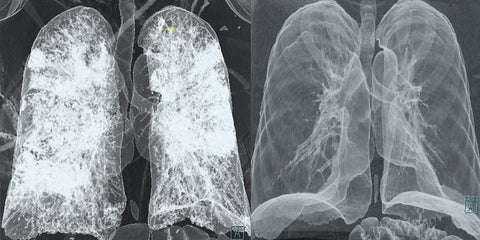

“I never thought that working hard to make a living could lead to such devastating consequences. After 20 long years of repairing roads for a construction company, all I have to show for it is a debilitating sickness that threatens my life every day. My lungs, once strong and healthy, are now riddled with pneumoconiosis, a disease caused by years of inhaling harmful dust particles. The dirt deposits in my lungs and fibrosis of my lung tissues have left me coughing up blood and struggling to breathe. The countless expensive medicines prescribed by my doctor were a fleeting hope, as they failed to provide any significant relief. But then I stumbled upon an herbal remedy that changed everything. At first, I was skeptical—how could a simple spray possibly heal me after so many failed attempts? But after just three days of using it, I began to feel a glimmer of hope. The relief it brought me was immense, and I could feel my body slowly healing. As I continued using the spray for at least one month, I gradually regained my health. I no longer snore, I no longer cough, and I no longer feel the constant discomfort of a foreign body in my airways. This herbal remedy, something I was once hesitant to believe in, has saved my life in ways I never thought possible. If you’re struggling with the same health issues as I was, I urge you to believe in this product and give it a chance. It may seem too good to be true, but it has worked wonders for me. Life may be unfair, but sometimes all it takes is a little bit of hope and the right remedy to turn things around.”

“I suffer from COPD, and I’ve been very concerned about my lung performance. Even after using an inhaler, I can hardly catch my breath. And my oxygen levels are always below 90 at night time. That’s why I’m glad I found Fivfivgo™. I’ve been taking it for about a month now, and my oxygen levels are above 90 all the time! In fact, I can breathe again, like I haven’t in a long time. I used to feel like I was breathing through a blanket or something. But that’s gone. And also, at night, I used to have this terrible mucus stripping down at the back of my throat and going into my lungs. I don’t have that anymore. I sleep a whole lot better. And the great thing about Fivfivgo™ is that it’s 100% natural and organic. So if you’re looking to be able to take a deep breath and get back into the swing of things in life like you used to, you want to get Fivfivgo™. Your lungs are going to be a whole lot better for it.”